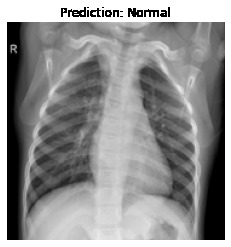

Currently, there is an urgent need for efficient tools to assess the diagnosis of COVID-19 patients. In this project, we propose a constructive solution for detecting and labeling infected tissues on CT lung images of such patients. To cut down false positives our model is trained on 4 types of lung CT images : COVID, Viral Pneumonia, Lung Opacity and normal images to get the best possible results with highest accuracy.

We built it using Tensorflow 2.x using Python. We have developed a Convolutional Neural Network model with an average accuracy of more than 85%.

We are proud that among the top 5 models, one of our models achieved 88.8% accuracy with very low loss.